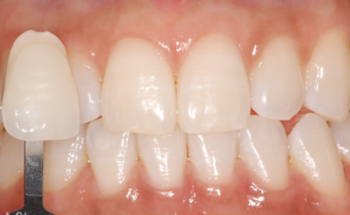

치아미백, 올세라믹 보철치료로 되찾은 자연스러운 앞니